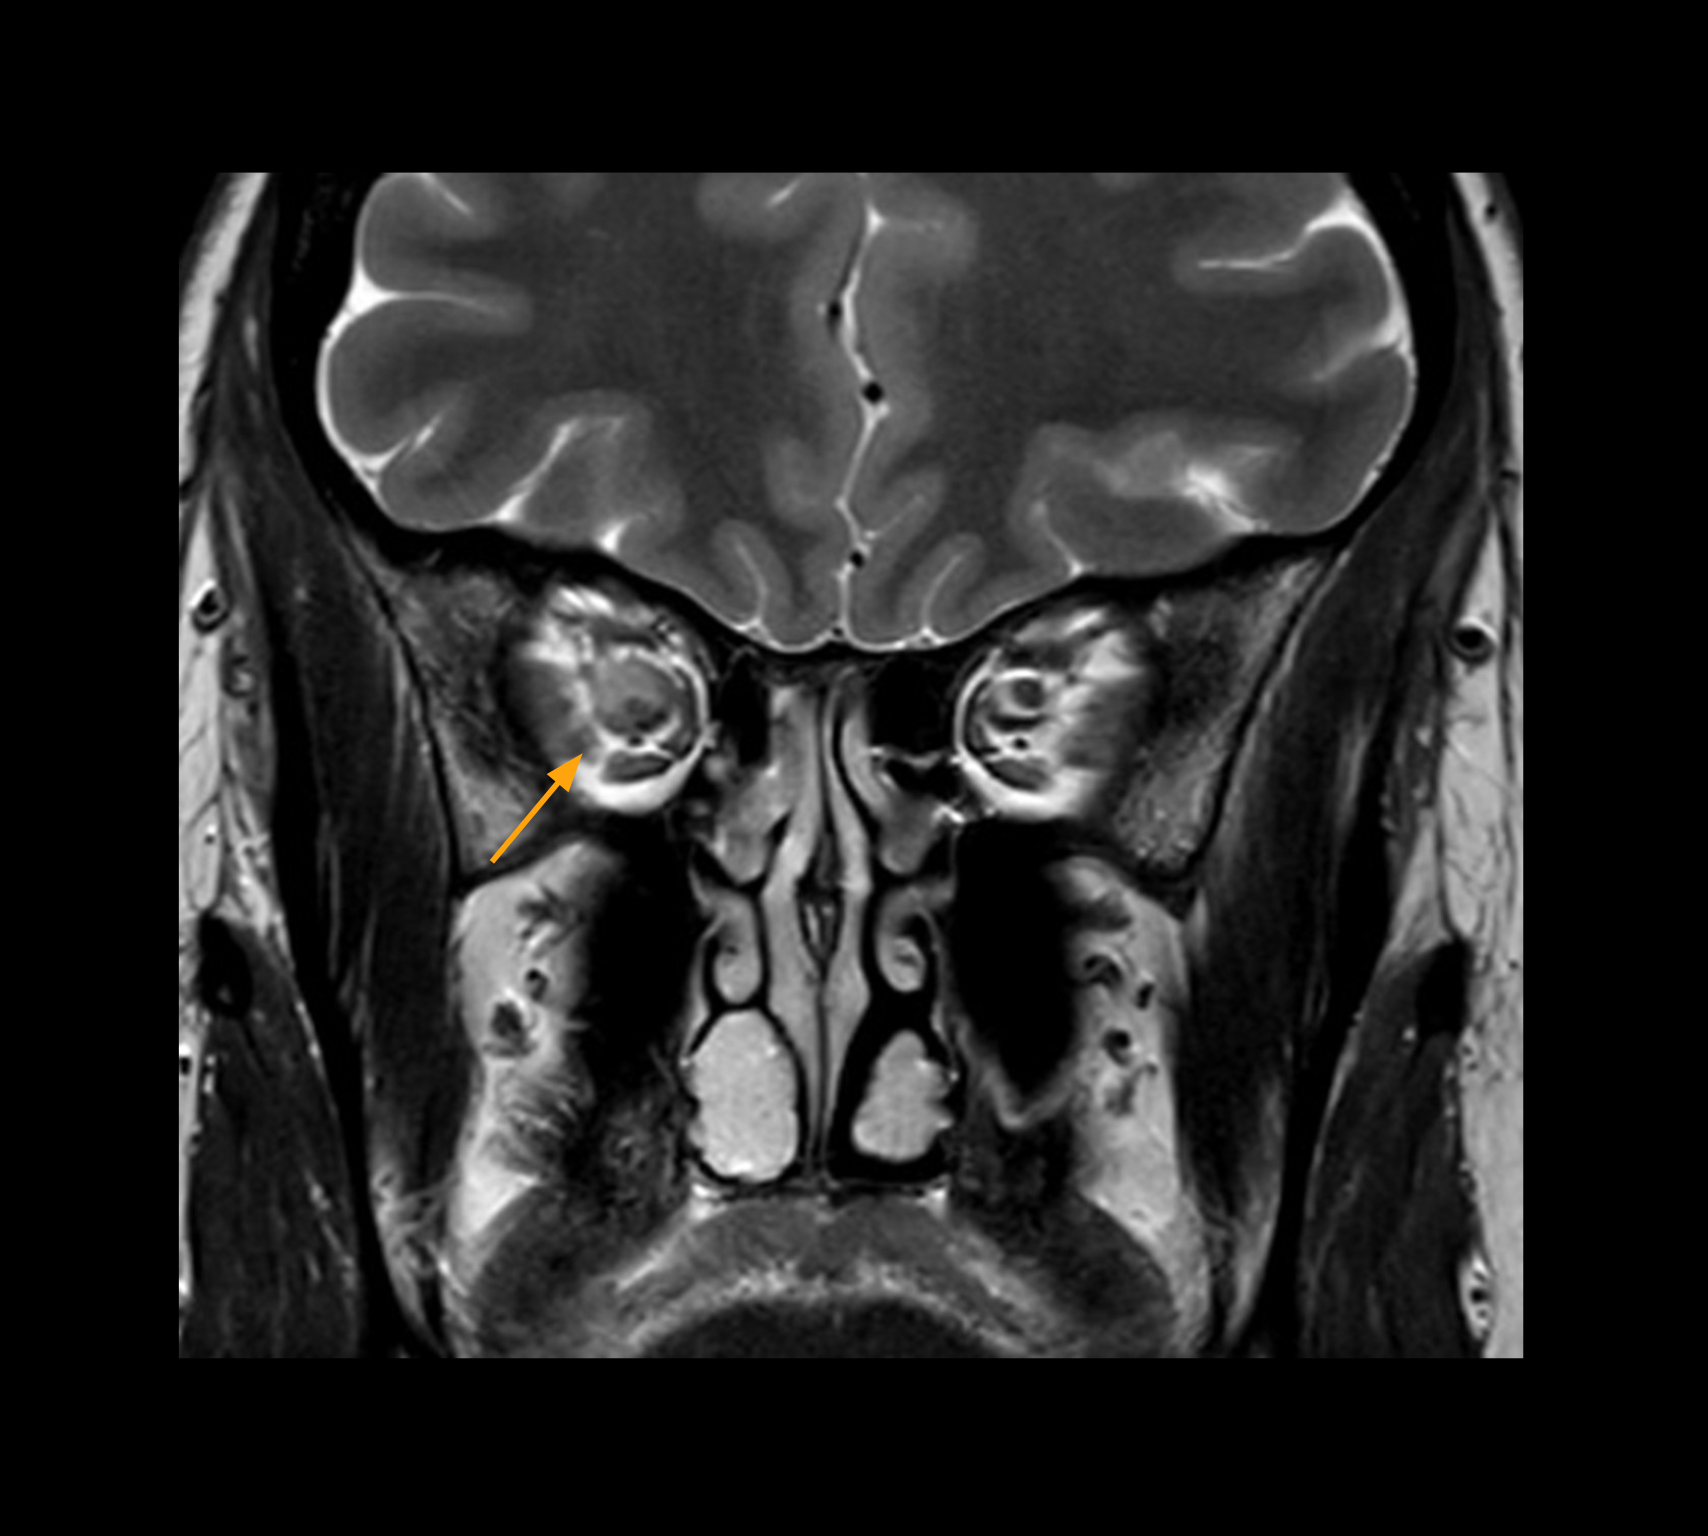

Imaging of the optic nerve sheath

High-resolution MRI impressively demonstrates the compression and narrowing of the right optic nerve in this case of optic nerve sheath meningioma (ONSM). The coronal T2-weighted images show the hyper-intense, half-moon shaped lesion, that is clearly visible in the axial T1W image after contrast injection (right). These imaging findings were so convincing that there sponsible neurosurgeon did not consider a pretherapeutic histological clarification.

High resolution-MRI impressively demonstrates the compression and narrowing of the right optic nerve in this case of optic nerve sheath meningioma (ONSM). The coronal T2-weighted images show the hyper-intense, half-moon shaped lesion, that is clearly visible in the axial T1W image after contrast injection (right). These imaging findings were so convincing that there sponsible neurosurgeon did not consider a pretherapeutic histological clarification.